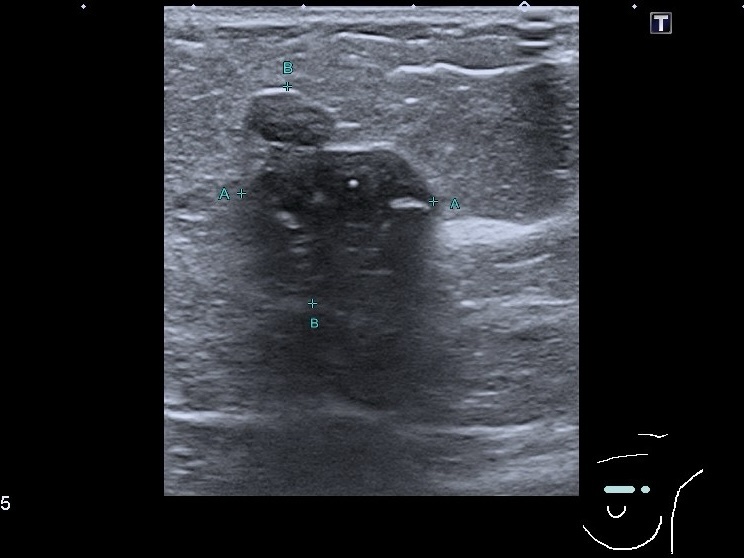

Если регулярно проходить диагностический контроль молочных желез, можно обнаружить первые подозрительные на рак признаки без распространения процесса на лимфатические узлы, другие органы. Недавно к нам обратилась женщина для профилактического контроля молочных желез. При проведении УЗИ было обнаружено образование неправильной формы гипоэхогенное образование с кальцинатами ,с нечёткими неровными контурами, с акустическим эффектом заднего затухания(тени). При этом васкуляризации не было выявлено. Регионарные лимфатические узлы, состояние кожи были без патологических изменений. Это образование чётко видно на сканах. Пациентка была отправлена на биопсию. Мы предполагаем, что всё у неё вовремя выявлено и будет пролечено.